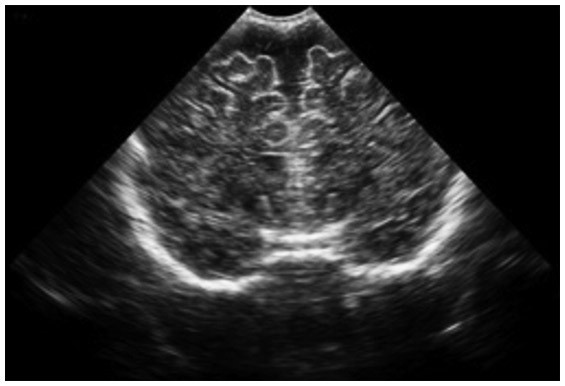

Нейросонография — это ультразвуковое исследование головного мозга, которое проводится через родничок. Пока у ребёнка не закрылся мягкий участок на темечке, через него можно смотреть прямо в мозг: без наркоза, без облучения, без боли. Исследование входит в плановый чек-ап в один месяц, а при необходимости может проводиться с первых часов жизни.

К наиболее частым изменениям, обнаруживаемым при НСГ, относятся: увеличение ширины боковых желудочков мозга, расширение субарахноидальных ликворных пространств, наличие псевдокист сосудистых сплетений, признаки структурной незрелости мозга.

- Наружное расширение: ликвор скапливается снаружи мозга, между корой и оболочками, расширяется субарахноидальное пространство, увеличивается межполушарная щель. Часто сопровождается ускоренным ростом окружности головы. Врачи нередко квалифицируют это как «доброкачественное» и рекомендуют наблюдение. Иногда так и есть. Но это не означает, что наблюдение можно вести формально.

- Вентрикуломегалия: расширение желудочков мозга — внутренних полостей, где ликвор вырабатывается и откуда должен оттекать. Это другой механизм и другой уровень настороженности. Желудочки расширяются, когда нарушен отток или повышено давление изнутри.

Личный опыт: между первой НСГ и чистым МРТ

В выписке Филиппа из роддома, первая НСГ в возрасте 1 месяц, стояло заключение: «эхографически, умеренное расширение наружных ликворных пространств». Я обратила внимание. Не поняла сразу, что это означает, но, невзирая на рекомендации годик подождать, задалась вопросом и начала делать контроль каждый месяц.

В два месяца картина изменилась: к расширению добавились мелкие псевдокисты правого сосудистого сплетения, субэпендимальная псевдокиста справа, изолированное расширение межполушарной щели. К двум годам четырём месяцам прошли расширенное обследование. НСГ провели транскраниально, через височные кости, поскольку родничок к тому времени уже закрывался, и выявили вентрикуломегалию лёгкой степени и признаки внутричерепной гипертензии. УЗДГ показало венозную дисгемию, ЭЭГ — нарушение метаболизма нейронов и ирритацию коры, АСВП — снижение фонематического слуха.